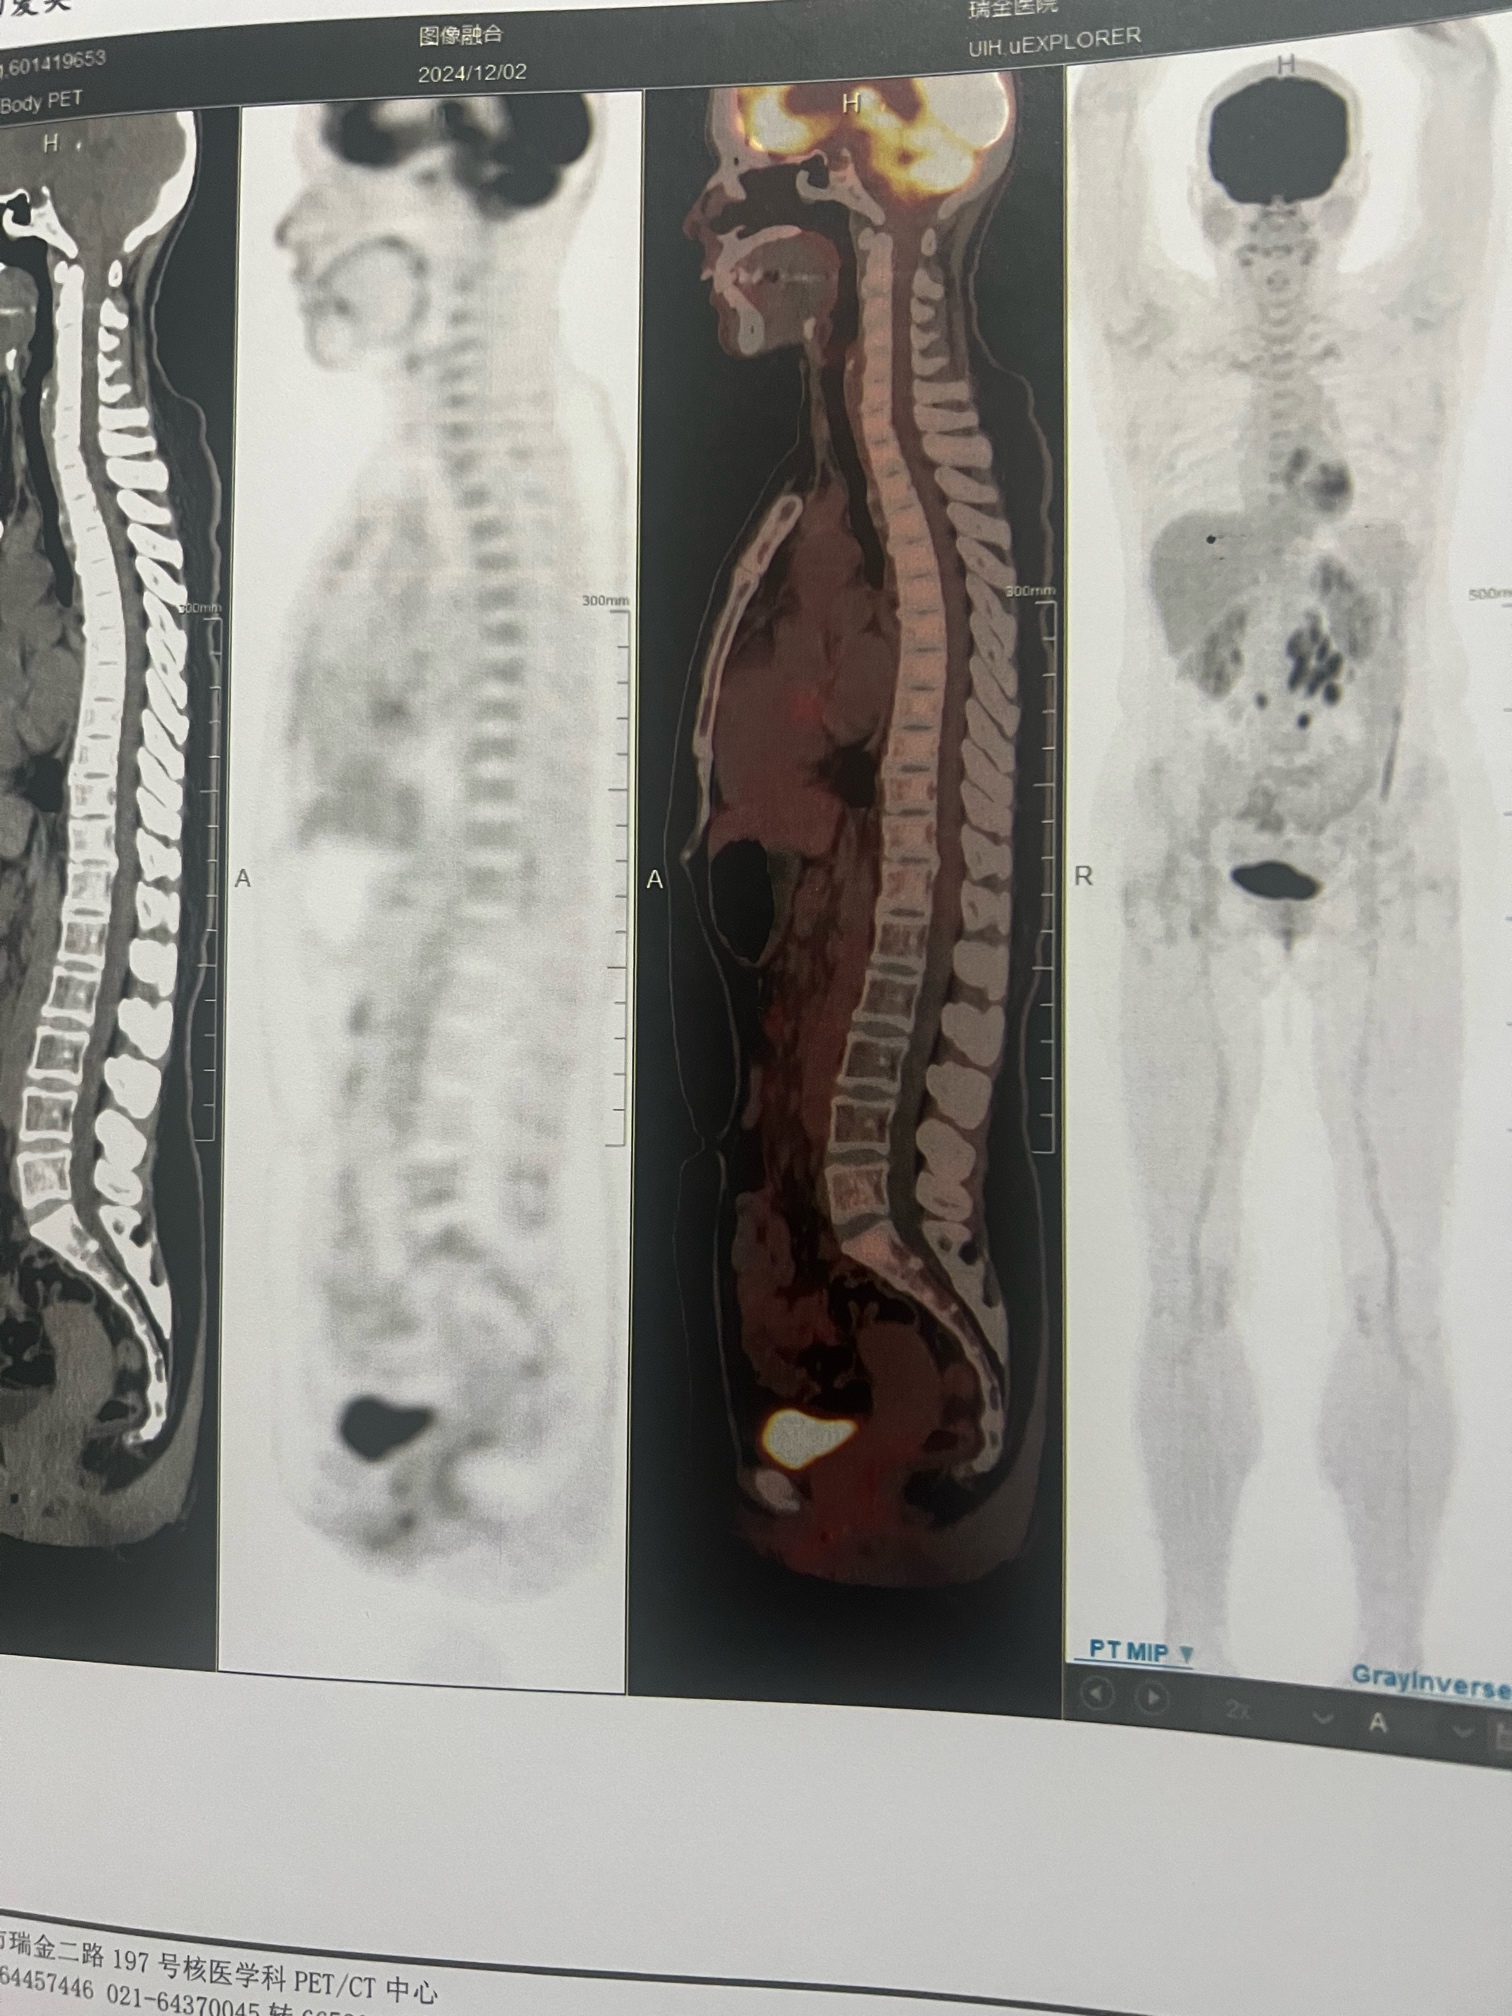

- 滤泡性淋巴瘤1-2级

赛利尼索没有批准这个适应症,也许行,也许不行。总的来说病理不是很明确,到底初治的时候是否伴有大B转化,到底应该是当成侵袭性淋巴瘤来治疗,还是当成惰性淋巴瘤来治疗,思路也不清楚。做了三个R-CHOP,后来是R2和放疗,现在还是没有完全缓解,用R-GDP的目的,是为了下一步自体移植做准备吗?来那度胺用的时间超过4个月的话,采集干细胞会比较困难。 |